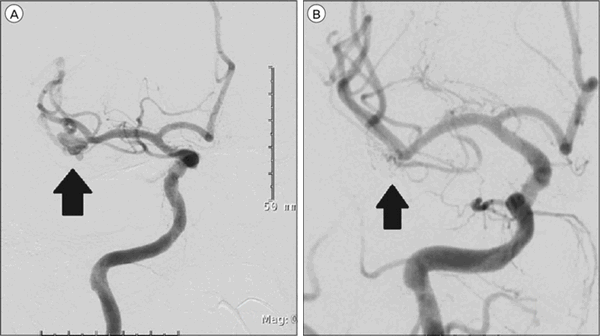

Клипирование аневризмы СМА из контралатерального доступа выполнено у одного больного с множественными «зеркальными» аневризмами обеих СМА (рис. 5). После клипирования разорвавшейся аневризмы правой СМА выполнен контралатеральный транссильвиевый доступ к аневризме левой СМА. Выделенная аневризма была милиарного размера и имела широкую шейку, распространяющуюся на крупную височную ветвь СМА. При помощи ВЭСА удалось осмотреть аневризму под большим увеличением, исключить связь ее тела с перфорирующими ветвями и после клипирования убедиться в проходимости височной ветви СМА. В данном наблюдении контралатеральный подход к АА СМА позволил избежать трепанации черепа с противоположной стороны и, фактически, второй операции.

Рис. 5. Клипирование аневризмы контралатеральной средней мозговой артерии с использованием видеоэндоскопической ассистенции у больного П., 33 года, на 24-е сутки после субарахноидального кровоизлияния. а, б — право- и левосторонняя каротидные ангиограммы: аневризмы М1-сегментов правой и левой средних мозговых артерий (обозначены стрелками); в — вид структур контралатеральной сильвиевой щели через микроскоп; г, д — вид через эндоскоп с тубусом 0°: аневризма средней мозговой артерии в области устья темпорополярной ветви; е — вид через микроскоп: аневризма клипирована; ж — вид через эндоскоп с тубусом 30°. Клипса точно расположена на шейке аневризмы, темпорополярная ветвь средней мозговой артерии не компримирована. 1 — левый зрительный нерв, 2 — правый (контралатеральный) зрительный нерв, 3 — правая средняя мозговая артерия (контралатеральная), височная ветвь правой средней мозговой артерии, 5 — аневризма правой средней мозговой артерии, 6 — шпатель на базальной поверхности правой лобной доли мозга, 7 — правая лобная доля мозга, 8 — клипса на шейке аневризмы.